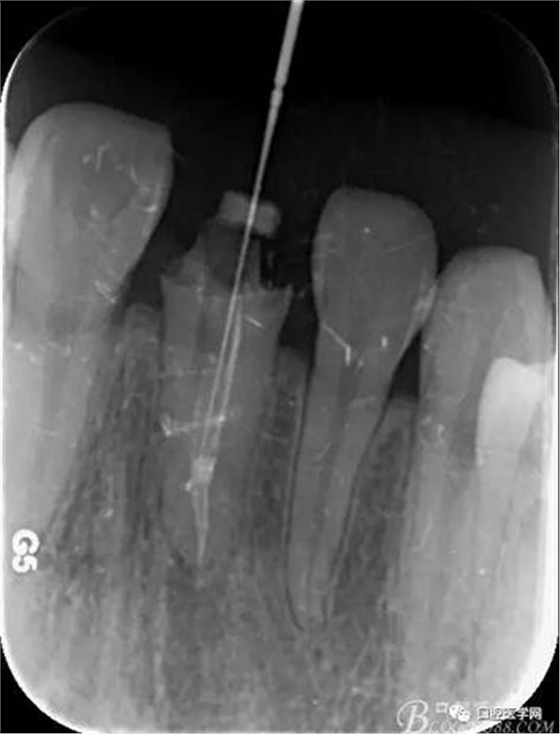

輔助檢查:X線見根尖區(qū)輕低密度影像,根尖1/3見根充物密實恰填,根管上2/3見折斷纖維樁,與根管密實。

三:保留根尖1/3原有材料封閉,去除根管上2/3的纖維樁,預(yù)備樁道。

術(shù)前X線片